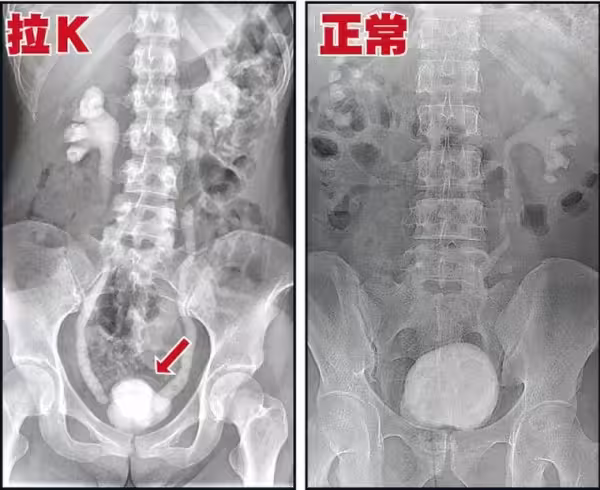

其實吸食K他命長久的人,必然會有這種尿頻、尿急、尿痛的症狀,

這是由於K他命的獨特性,持續傷害人體的泌尿系統,導致的嚴重後果。